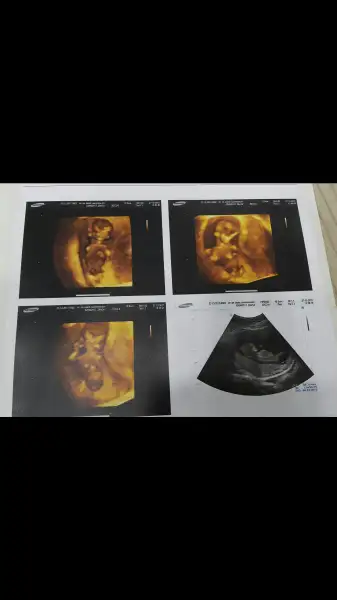

Kızlar buda benim ponçiğim bi türlü resmini koyamamıştım ama sonunda başardım. Ikili tests gunu cekilmis fotolari 11+6 idi o gun ama ultrasonda 12+3 çıķmıştı. Doktor erkege benzio demisti dikkat ettimde resimde bülüşünü gördüm ben sağ üstteki resmde